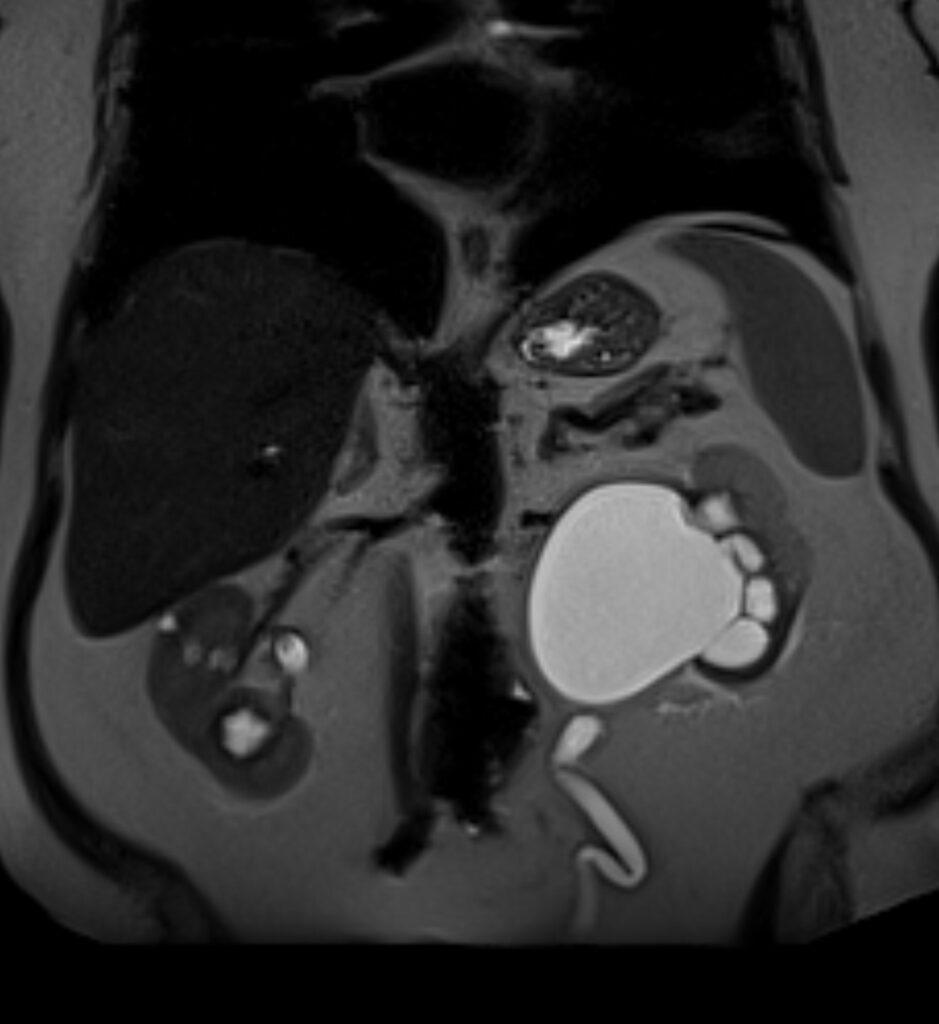

MR images revealed the left dilated ureter and intraluminal polypoidal masses at its distal segment. Associated moderate left hydronephrosis is noted.